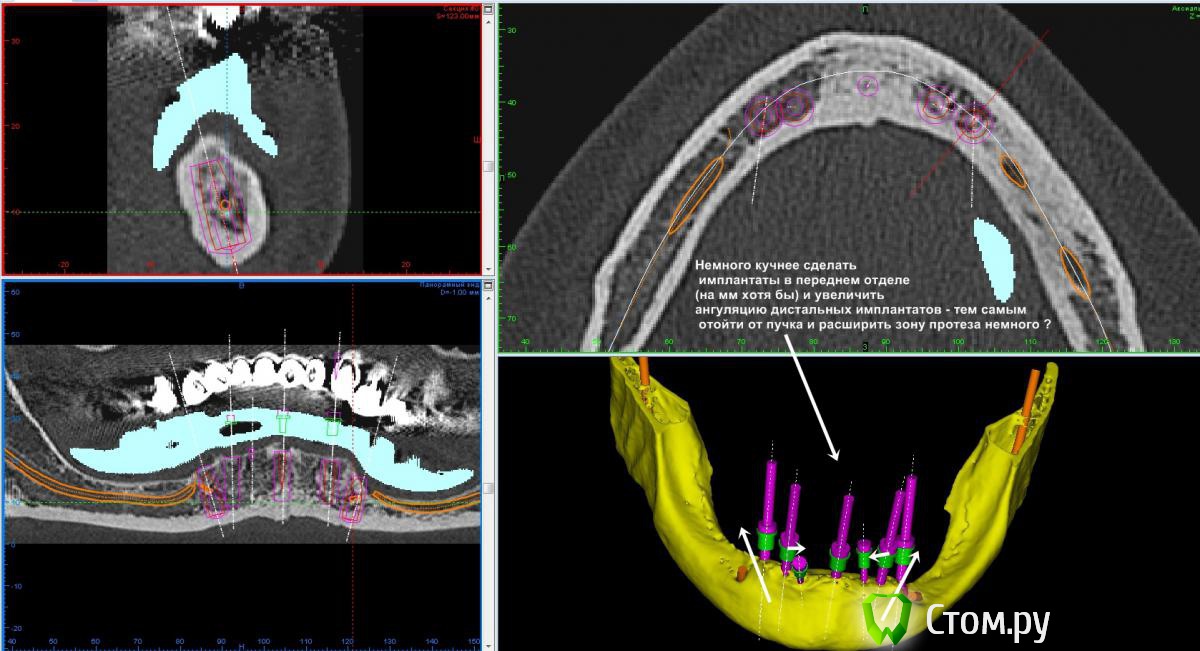

Игорь Пеликан Опубликовано 19 января, 2014 Поделиться Опубликовано 19 января, 2014 Прошу поделиться своими мыслями по поводу хирургической реабилитации(костная пластика) девушки 35 лет,все это покрыто двумя сьемниками.Верх-2 сектор оставляем,в 1 секторе синус,3D.Низ-закапываются сомнения в васкуляризации графта в дистальных отделах, 3D или репозиция,не хочется воспользоваться только междументальным расстоянием? Ссылка на комментарий

АнтонТЛТ Опубликовано 19 января, 2014 Поделиться Опубликовано 19 января, 2014 Можно, но будет ли в данном случае прирост на нужную высоту или будет просто операция ради операции?В данном случае поставил бы в передний отдел без дополнительных костных пластик и переносов нерва. 1 Ссылка на комментарий

Mane Опубликовано 19 января, 2014 Поделиться Опубликовано 19 января, 2014 Можно, но будет ли в данном случае прирост на нужную высоту или будет просто операция ради операции?В данном случае поставил бы в передний отдел без дополнительных костных пластик и переносов нерва.теперь мысль ясна. а то я подумал что в принципе нельзя вырастить.конечно 1 сантиметр за 1 раз здесь не вырастить Ссылка на комментарий

dent-a Опубликовано 19 января, 2014 Поделиться Опубликовано 19 января, 2014 яб воттак сделал - но тут пациентка под 60лет Ссылка на комментарий